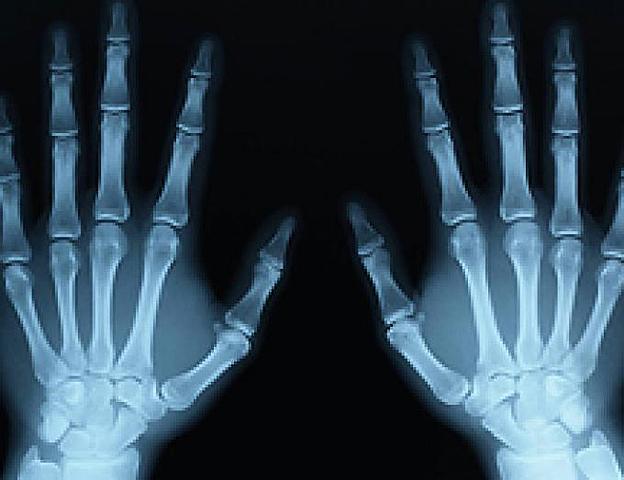

• RAYOS X

RAYOS X

W.C. Roentgen descubre los rayos X. Los rayos X son actualmente un gran apoyo para el diagnóstico oportuno de enfermedades, debido a la facilidad de detectar anomalías estructurales, un descubrimiento impactador. Casio, P.. (Julio 06, 2015). Historia de los rayos X. Agosto 25, 2019, de sobrehistoria.com Sitio web: https://sobrehistoria.com/